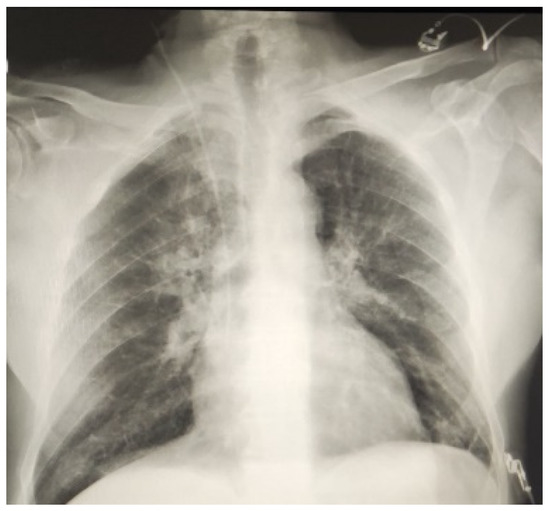

A Single Center Initial Experience with Robotic-Assisted Minimally Invasive Coronary Artery Bypass Surgery (RA-MIDCAB)

Operative Set-Up and Strategy